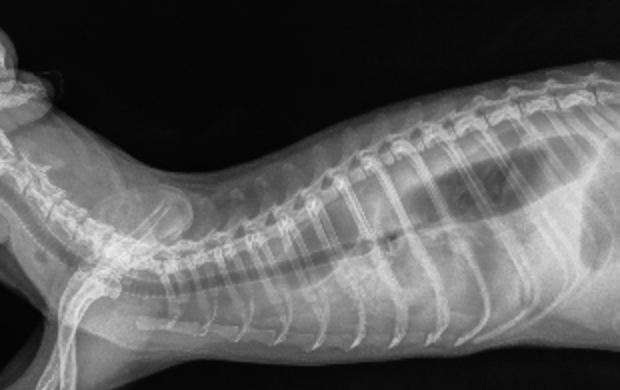

Результаты анализов крови и ультразвукового исследования брюшной полости не показали наличия патологий.Рентгенография грудной полости: обнаружена аномалия в виде мегаэзофагуса – патологического расширения пищевода.

Рентгеноскопия акта глотания была выполнена для оценки функций пищевода и кардиального сфинктера. Выявлены гипотония и расширение пищевода на всем протяжении до 18 мм, S-образный изгиб пищевода в средней трети и спазм или стриктура кардиального сфинктера (видео 1). В течение 25 минут незначительное количество кормовых масс сместилось из пищевода в желудок.